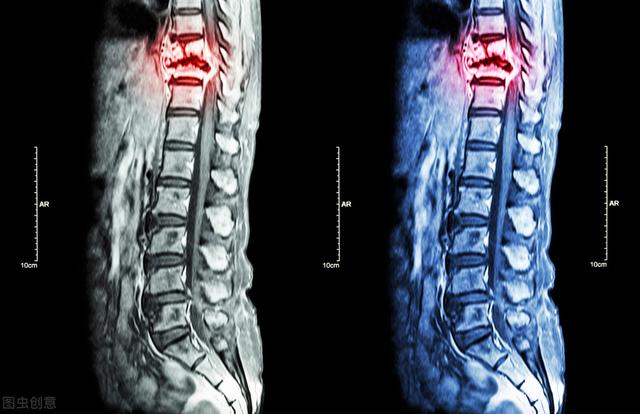

Magnetresonanztomographie von Knochenmetastasen

Nachweis von Knochenmetastasen in der Brustwirbelsäule